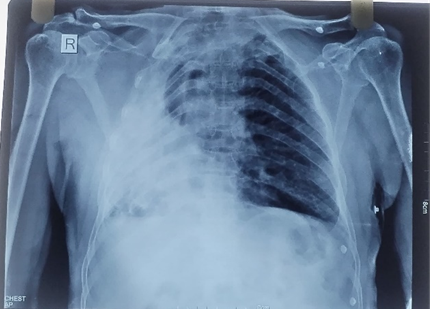

Coronary angiography demonstrated essentially normal coronary arteries. Chest radiographyconfirmed a destroyed right lungwith amild rightward mediastinal shift. ECGcontinued to show persistent ST elevations. Laboratory investigations showed: Hemoglobin: 8.8 g/dL (indicating mild anemia), White blood cell and platelet counts: within normal limits, Serum creatinine: 1.0 mg/dL (normal), Mild elevations in serum sodium and potassium levels.

Fig 03: Chest X-Ray

Despite the initial concern for ACS, subsequent evaluation did not reveal any significant obstructive coronary pathology. The chest discomfort was attributed, in part, to underlying anatomical distortion due to post-tubercular structural lung damage and cardiac displacement.The patient was managed conservatively with antiplatelets, anticoagulants (heparin), antibiotics, and antihypertensive medications. He was thoroughly counselled regarding the anatomical findings, the benign nature of the current cardiac evaluation, and the potential impact of his past pulmonary pathology on current symptoms. After two days of observation and supportive care, his chest pain resolved completely, and he was discharged in stable clinical condition.